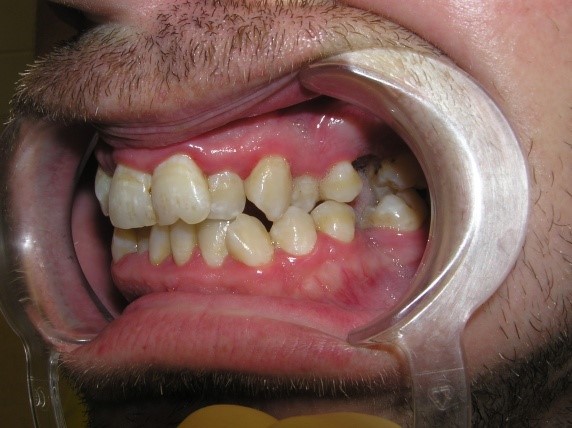

Pic.26. Crowding of the front teeth of the upper and lower jaws.